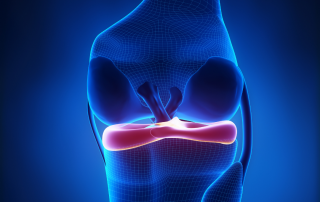

Menüsküs yırtığının neden olduğu ağrı duruma göre değişiklik gösterebilir. Menüsküs yırtığı olan hastalarda genellikle diz